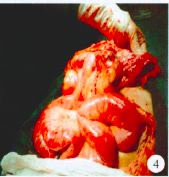

术中见:①疝囊位于耻骨上约5 cm,约15 cm×15 cm×15 cm 大,疝囊颈约12 cm×10 cm×5 cm 大(腹膜明显增厚),疝囊内见大量脓性渗出,疝内容物为嵌顿回肠(长约60 cm),充血水肿明显,色暗,较多脓苔附着;距回盲部约50 cm 处小肠与疝囊底致密粘连,包裹并形成梗阻,可见斑片状坏疽穿孔,近段小肠扩张,积气及积液(图3)。②腹、盆腔各间隙可见大量脓性渗出约400 ml,部分空肠呈“U”状与上腹部切口下致密粘连(图4)。③结肠腔内大量干结大便。

图 3 探查见小肠与疝囊底致密粘连、包裹并形成梗阻,近段小肠扩张,积气、积液